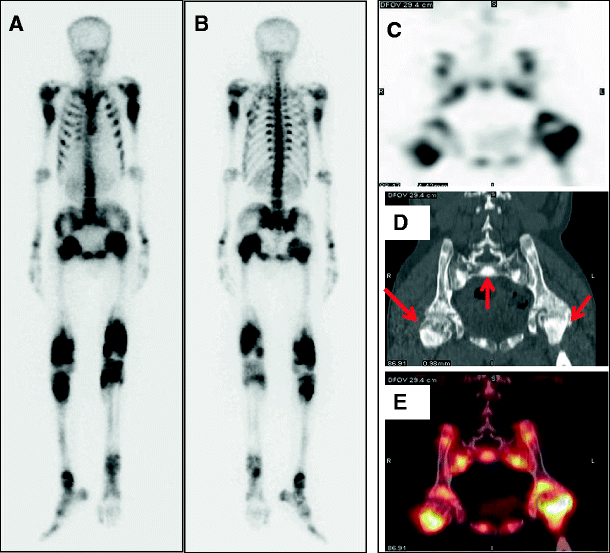

From link.springer.com

Bone Scan and SPECT/CT Findings in Marble Bone Disease SpringerLink Define Marble Bone Disease osteopetrosis, or marble bone disease, is a rare skeletal disorder due to. ‘osteo’ means bone, and ‘petrosis,’ meaning stone. Therefore, the disease is often. osteopetrosis is a congenital metabolic bone disease caused by defective osteoclastic resorption of immature bone that presents with. osteopetrosis is group of a rare disorders that cause bones to grow abnormally and. Define Marble Bone Disease.